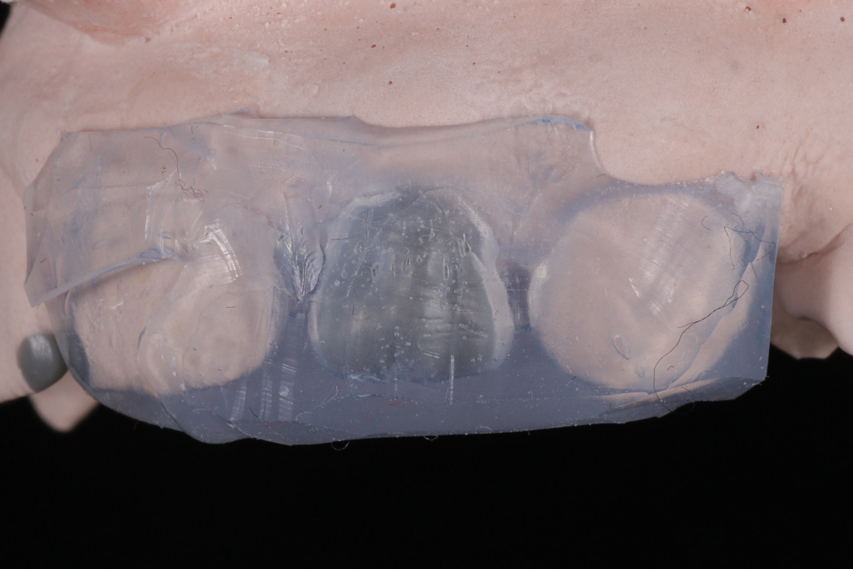

In order to verify the thickness of the enamel mass that would be created, three sets of putty guides were made: one for the incisal edge, one for occlusal control, and one for sagittal control (Figure 9 through Figure 14). The thickness of the enamel material that needed to be placed was 0.2 mm in the cervical third, 0.5 mm in the middle third, and 0.8 mm in the incisal third. In the incisal third, 1 mm was left occlusally.8,9 In addition, two sets of silicone indices were made-one based on the full wax-up and one based on the cutback wax-up (Figure 15 through Figure 18).

(15.) Silicone index of the full wax-up of teeth Nos. 7 and 10, respectively, on the model.

Figure 15

(16.) Silicone index of the full wax-up of teeth Nos. 7 and 10, respectively, on the model.

Figure 16

(17.) Silicone index of the cutback wax-up of teeth Nos. 7 and 10, respectively, on the model.

Figure 17

(18.) Silicone index of the cutback wax-up of teeth Nos. 7 and 10, respectively, on the model.

Figure 18